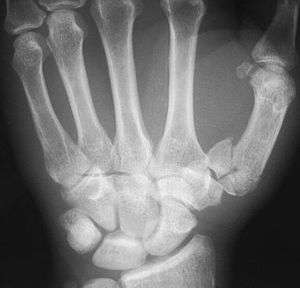

Fractures

Fractures to the first metacarpal bone account for 30-40% of all hand fractures and 25% of all metacarpal fractures (second to fractures to the fifth metacarpal bone). 80% of fractures to the first metacarpal occur at its base. [7]

Common fractures to the thumb metacarpal include Bennett's fracture and Rolando's fracture.